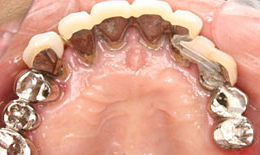

インプラント症例(4) 68歳 女性

治療前

上顎

保存困難な歯を抜歯後、インプラントを7本埋め込み、ボーンアンカードブリッジを装着した